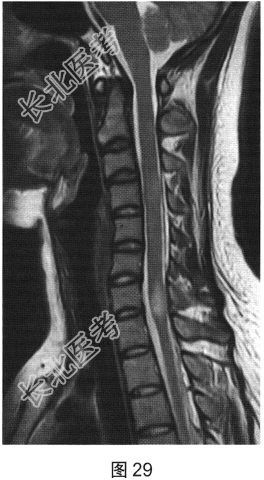

- [材料题] 患者女性,20岁,肢体无力2个月余。MRI检查结果如图27~图30所示。

- 多项选择题1.根据患者MRI平扫和增强的表现,其可能的诊断是( )

F、多发性硬化

- 多项选择题4.关于多发性硬化的诊断,叙述正确的是( )

A、“直角脱髓鞘征”是其较特征性的表现

B、脑内多发脱髓鞘病变

C、脊髓病灶多累及脊髓外周

D、病程呈复发.缓解交替

E、脊髓病灶多位于颈胸段脊髓

F、水肿及占位效应明显